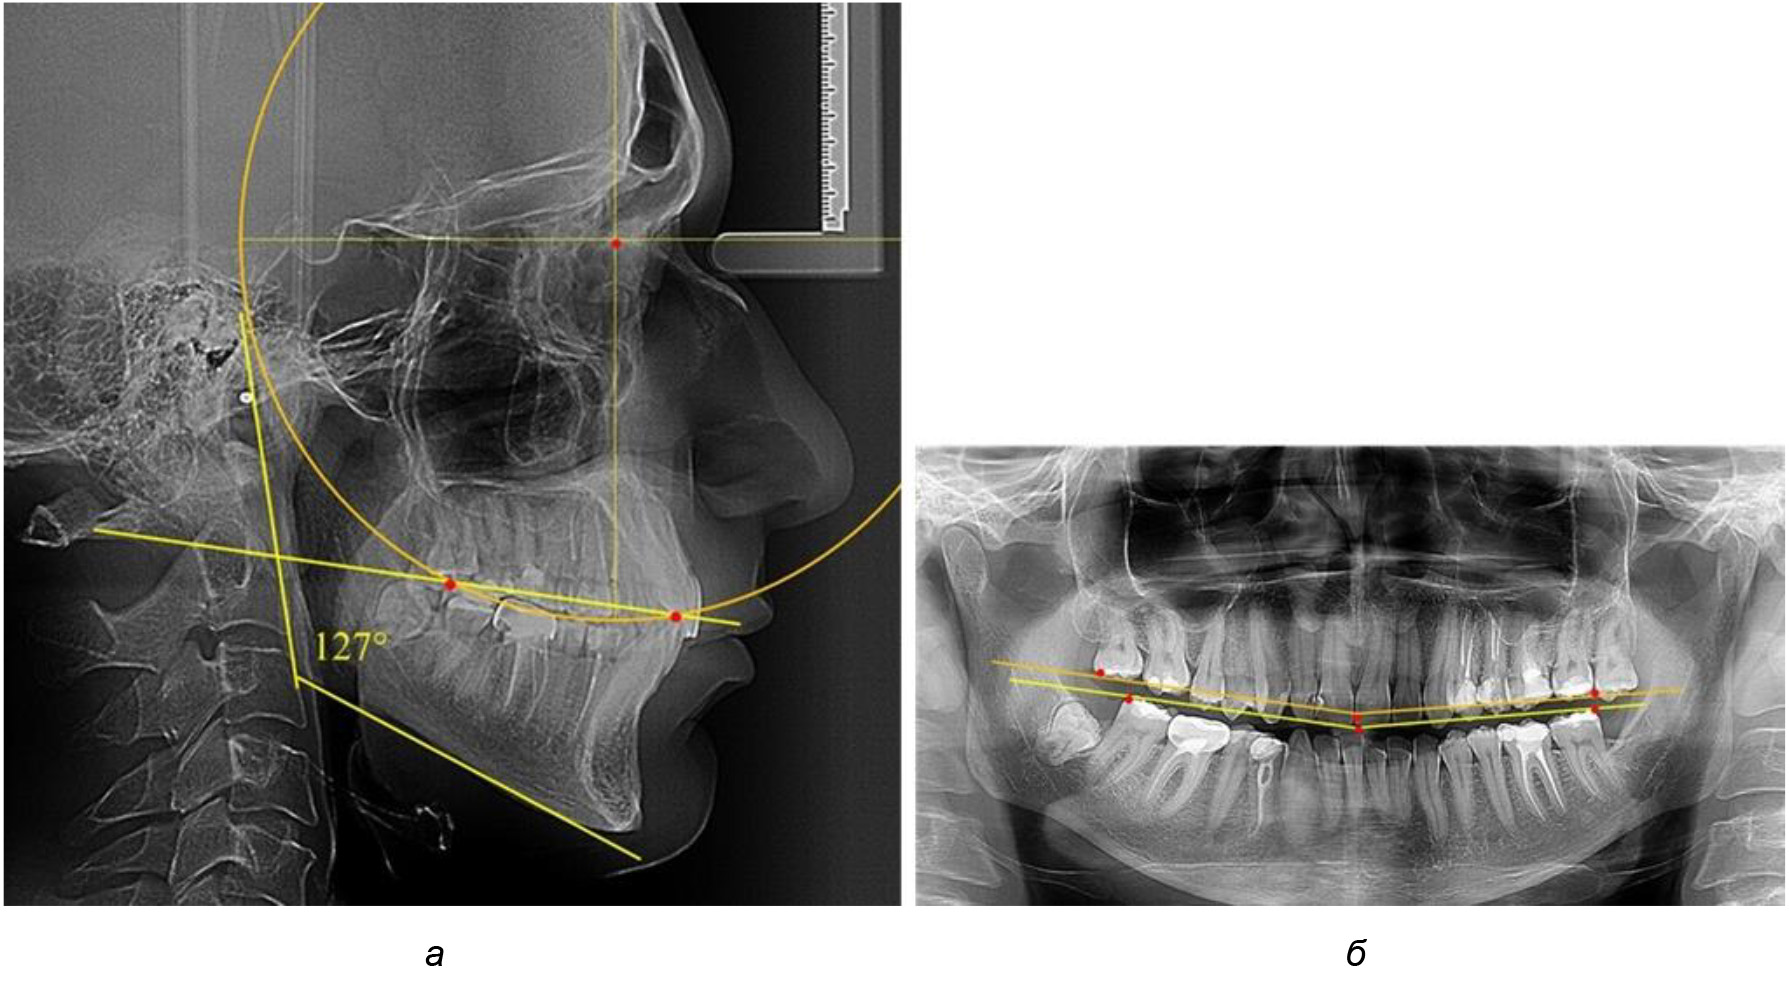

В ходе исследования установлено, что в 1-й подгруппу вошли ТРГ и ОПТГ 18 человек 1-й группы, что составило (29,03 ± 5,78) % от всех пациентов, рентгенограммы которых были проанализированы. У всех пациентов величина угла нижней челюсти была более 125° и в среднем составила (129,89 ± 3,62)° и характеризовала вертикальный тип нижней челюсти.

Деление величины радиуса круга к длине окклюзионной линии составило 1,623 ± 0,02. Таким образом, для определения радиуса окружности, соответствующей кривизне окклюзионного контура боковой ТРГ, необходимо измерить расстояние между передней и задней окклюзионными точками и последующим умножением полученной величины на число Фибоначчи (рис. 2).

Рис. 2. Особенности кривой Spee на ТРГ (а) и ОПТГ (б) у людей с признаками вертикального роста